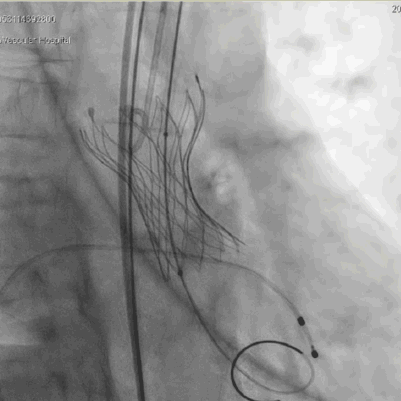

手术过程

主动脉根部造影,冠脉显影良好, 左冠切线位 20mm球囊预扩

“慢-快-慢”步骤释放瓣膜,20mm球囊后扩 瓣膜形态进一步优化

术后评估

球囊后扩后瓣膜形态良好

术前导管测量压差120mmHg;术后导管测量压差8mmHg